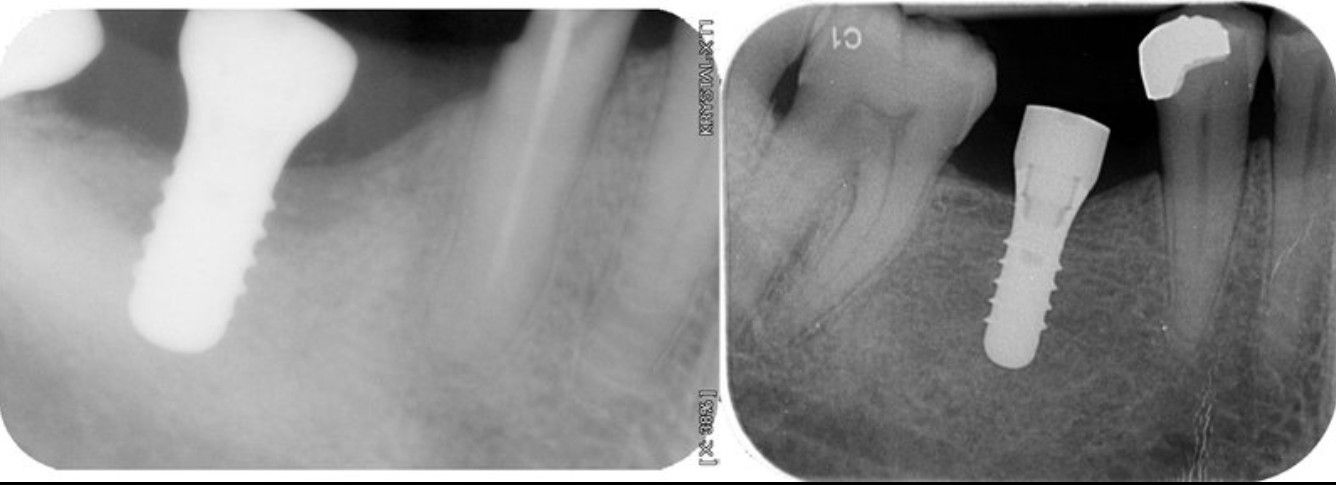

- Implantes Dentales

Nuestra clínica cuenta con equipamiento digital de última generación lo que permite trabajar en línea con Laboratorio Dental y obtener resultados más precisos y rápidos.